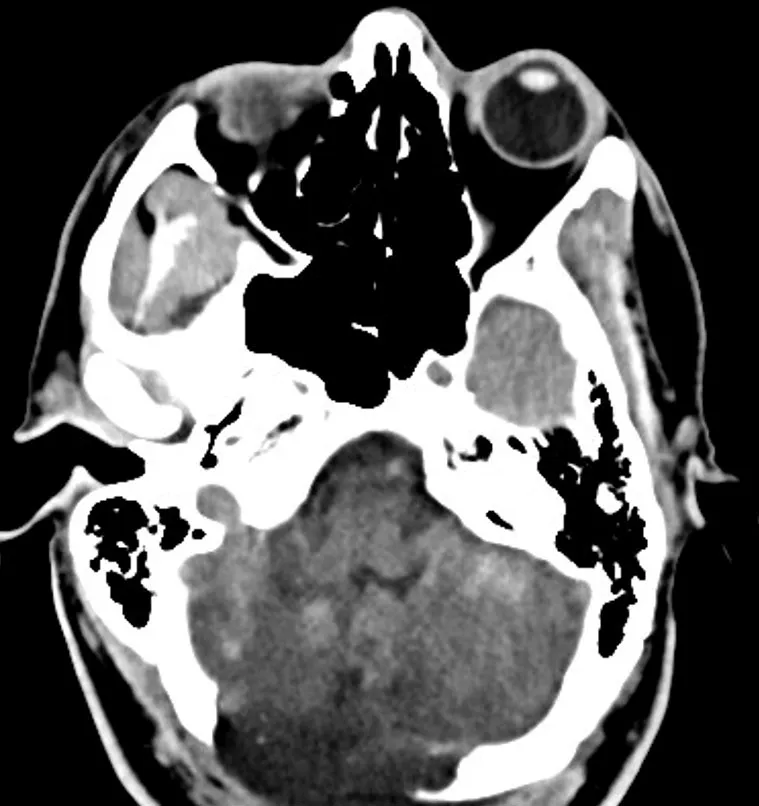

Approximately 12 hours after admission, the patient experienced a decline in his mental status, prompting a stat non-contrast computed tomography (CT) of the head which revealed bilateral cerebellar strokes. The associated cytotoxic edema resulted in significant mass effect on the 4th ventricle and early hydrocephalus.

Following the craniotomy, an emergent diagnostic angiogram was performed to evaluate for any residual thrombus of the basilar artery. The cerebral angiogram did not reveal a basilar thrombus but did confirm the aforementioned dissection. The patient was then placed on hypertonic therapy where he was monitored both clinically and with serial imaging. The patient was also monitored with continuous video electroencephalography (EEG) but no had no seizure activity.